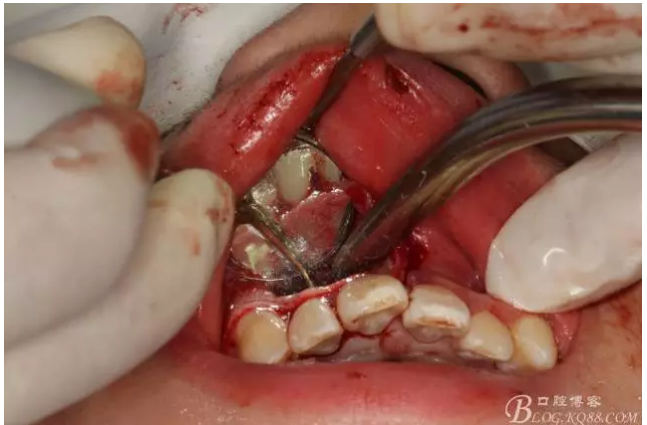

圖6.超聲骨刀切除根尖3mm。

圖7.切除根尖3mm的影像

圖8.根尖區(qū)超聲倒預(yù)備3mm

圖9.去除根尖3mm牙膠。